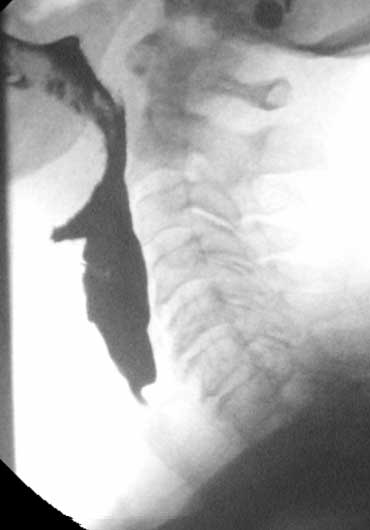

Ứ đọng (2)

Đây là bộ hình ảnh minh họa một bệnh nhân bị liệt các cơ khít hầu.

Tình trạng này thường đi kèm với giãn không đủ của cơ nhẫn hầu.

Trong ví dụ này, chúng ta có thể thấy bệnh nhân cố gắng bù đắp cho sự mất chức năng co bóp hầu bằng cách cử động quá mức của lưỡi và đầu.

Bệnh nhân này đang trong tình trạng căng thẳng cực độ, vì biết rằng khi bắt đầu thở mà cổ họng chưa trống, sẽ bị hít sặc.

- 1-3. Không thấy co bóp của thành sau hầu họng. Cơ nhẫn hầu không mở đúng cách.

- 4-7. Thuốc cản quang vào thanh quản nhưng không vào khí quản.

- 8-10. Cử động đầu quá mức nhằm đẩy bolus vào thực quản.

Trong một số trường hợp này, phẫu thuật cắt cơ nhẫn hầu là giải pháp duy nhất để tạo điều kiện cho thức ăn đi vào thực quản.